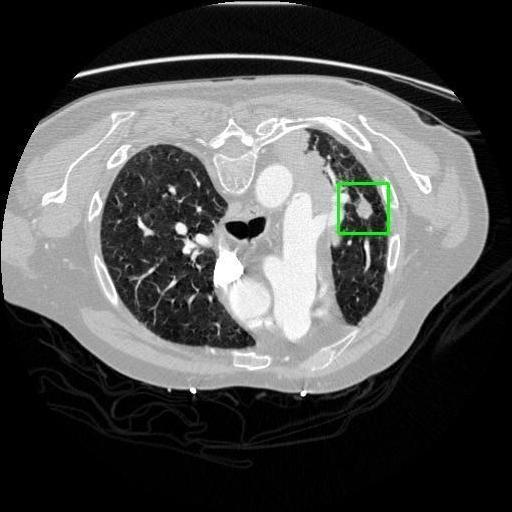

We developed an AI-based system using deep learning models for analyzing lung CT scans to detect and classify pulmonary nodules. We chose the YOLOv11 architecture for its enhanced object detection capability and adapted it specifically for medical imaging, incorporating pixel-level precision and severity classification.

Classification into three severity levels with colored bounding boxes.

Designed a severity classification system that categorizes nodules into null, moderate, and severe using colored bounding boxes, assisting in rapid clinical decision-making.